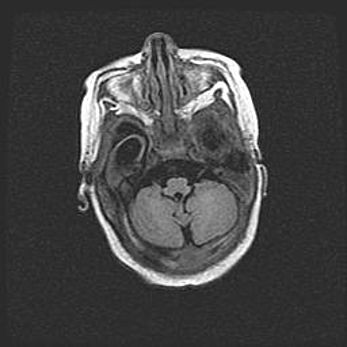

Церебральная ишемия II.

Возраст: 5 дней

Вес: 3400 г

Пол: женский

Окружность головы: 35 см

Срок гестации: 39 недель

Церебральная ишемия – это заболевание, характеризующееся недостаточностью (гипоксией) либо полным прекращением (аноксией) снабжения мозга кислородом по причине закупорки одного или нескольких сосудов. Это приводит к  что метаболическим расстройствам различной степени тяжести в тканях головного мозга, развитию коагуляционных некрозов и гибели нейронов.